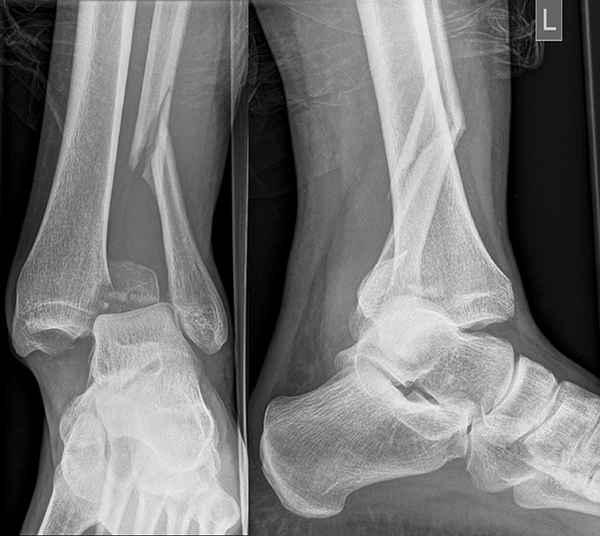

Die Standard-Röntgenaufnahmen des oberen Sprunggelenks bestehen aus drei Aufnahmen: der antero-posterioren Aufnahme (ap), der antero-posterioren Aufnahme mit Innenrotation des Unterschenkels von 20° („Mortise view“), sowie der streng seitlichen Aufnahme (siehe S2-Leitlinie Sprunggelenksfraktur). In der Röntgen-Bildgebung sollte neben den klassischen Frakturzeichen die Integrität der Syndesmose beurteilt werden. Dies erfolgt über die Beurteilung der Breite des lateralen und medialen Gelenkspalts („medial clear space“), des tibiofibularen Abstands 1cm oberhalb des OSG-Gelenkspalts („tibiofibular clear space“), bzw. der tibiofibularen Überlappung. Eine Verbreiterung des tibiofibularen Abstands über 5 mm oder die Erweiterung des medialen Gelenkspalts können Zeichen einer begleitenden Syndesmosenverletzung sein. (Abbildung 3) 6.

Liegt eine Fraktur des oberen Sprunggelenks vor, ist sowohl zur Entscheidung für ein konservatives oder operatives Vorgehen, als auch zur Operationsplanung, ein ausreichendes Verständnis der Fraktur und ihrer Morphologie notwendig. Insbesondere bei komplexen Verletzungen ist dafür die konventionelle Röntgenaufnahme in vielen Fällen nicht ausreichend. So konnten z.B. Black et al. zeigen, dass die operative Strategie zur Versorgung von OSG-Frakturen in 24% basierend auf einer zusätzlichen CT-Bildgebung relevant geändert wurden 7. Dies betraf die Lagerung, die Wahl des Zuganges und die Art der osteosynthetischen Versorgung. Besonders häufig änderte sich das Vorgehen bei Verletzungen des medialen (21%) und des posterioren Malleolus (15%). Darüber hinaus führten dislozierte (dislozierte Frakturen 31% vs. nicht-dislozierte Frakturen 20%) oder komplexe Frakturen (Trimalleolar-Frakturen 29% vs. Unimalleolar-Frakturen 10%) besonders häufig zu relevanten Änderungen des operativen Vorgehens. Die Computertomographie ist daher, insbesondere bei Bi- und Trimalleolar-Frakturen, essentiell für das Verständnis der Fraktur und somit für die Planung und Durchführung der Operation. In Abbildung 4 und 5 sind exemplarisch ein Röntgen- und ein CT Befund gegenübergestellt.